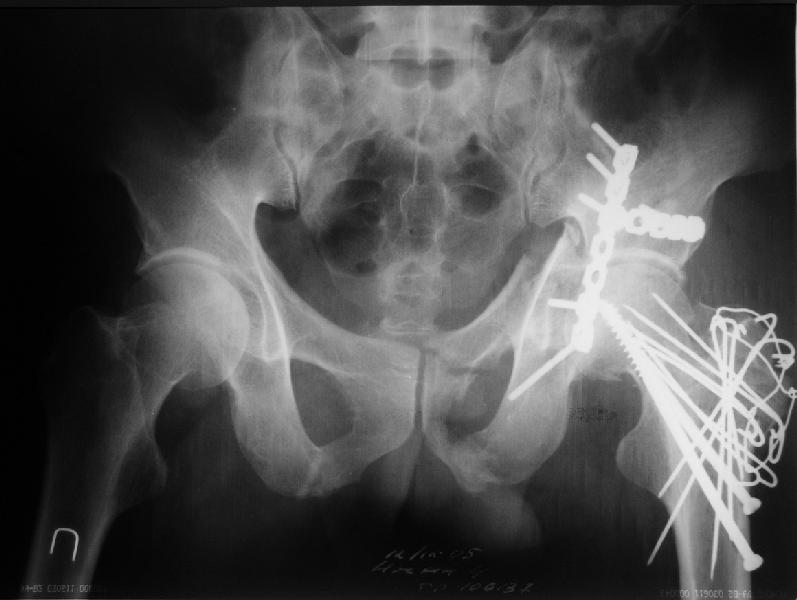

Уважаемые коллеги. Больной был оперирован в одну сессию 25 августа. Сначала на голень наложен спице-стержнвой аппарат. Затем выполнен остеосинтез вертлужной впадины Y-образным доступом. Пришлось дополнительно отсекать вертел. Шейка синтезирована спонгиозными винтами и спицами, вертел - спицами и стягивающей петлей. После операции находился на вытяжении 3 нед. Раны зажили первичным натяжением. Сейчас уже дома. Будет и дальше без нагрузки на левую ногу. Будем наблюдать в динамике. Ждем комментарии.

Перелом шейки был многооскольчатйй очень медиальный, по сути шейку и вертел расколотило об подвздошную кость с кучей мелких фрагментов, вертел был полностьб вовлечен в перелом, головка заподлицо скрывалась в расширенной вертлужной впадине. Качество кости приличное. Остатки дуги Адамса с предварительно проведенными винтами я вколотил в головку и компрессировал винтами - оказалось прочно, но образовался дефект верхнего отдела шейки, который был заплнен фрагментами фиксироваными трансфрактурными спицами - отсюда пучек.

Вертел во время доступа пришлось еще рубить, т.к.

переломы распространялись чересчур дистально.

Отсюда еще пучек спиц.